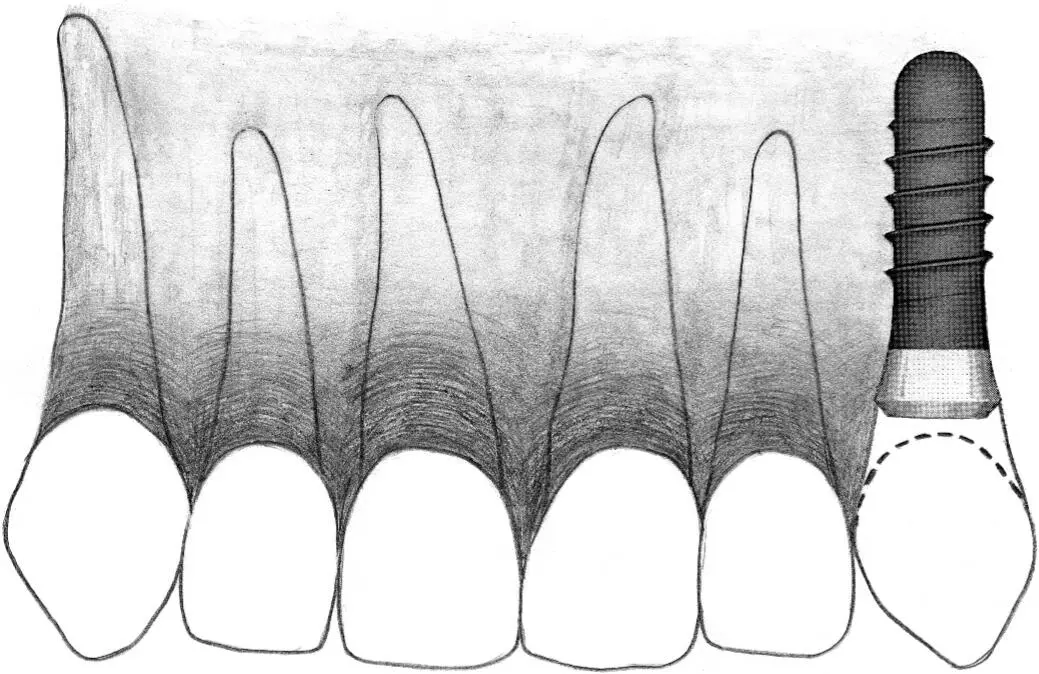

Fig 2-5 Narrow neck implant.

Fig 2-5a A narrow neck implant is indicated to replace a missing lateral incisor where the single-tooth gap offers limited space.

Fig 2-5b Another indication for a narrow neck implant is to replace missing mandibular incisors where available tooth space is likewise restricted.